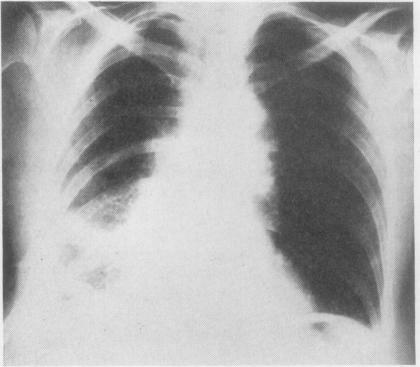

GINGELL J C

Thorax. 1965 May;20(3):261-9. doi: 10.1136/thx.20.3.261.